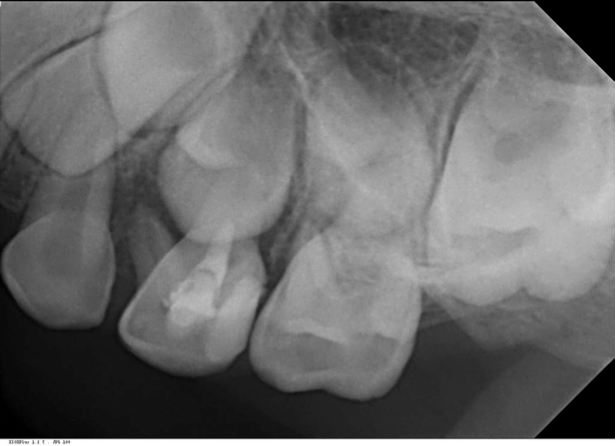

Post-op image following a pulpotomy, allowing the roots of the primary tooth to continue to develop.

One of the ideal ways to save primary teeth is vital pulp therapy. Recently, ProRoot MTA was cleared by the FDA for use in both pediatric pulpotomies and pulp capping. “In primary teeth or teeth that are under-developed, pulp capping with MTA allows for continued development of the tooth roots potentially getting us out of the adolescent stage and into adulthood where the teeth are more developed as opposed to a premature extraction,” Dr. Damas said.